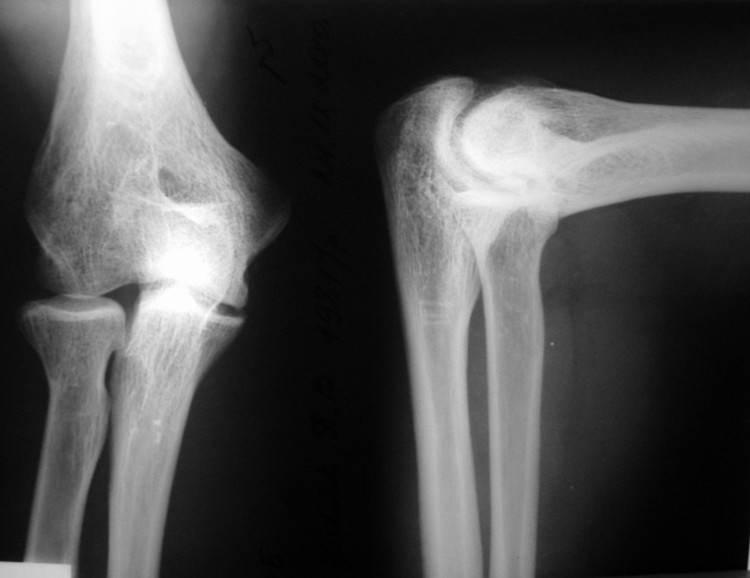

Мужчина, 29 лет. В 15 лет - спортивная травма, закрытый чрезмыщелковый перелом правой плечевой кости со смещением. Лечился консервативно. В настоящее время предъявляет жалобы на ограничение сгибания, повышенную утомляемость.

Объективно: сгибание до 100 гр., разгибание до 170. Неврологических и циркуляторных расстройств нет.

Вопрос: возможность хирургического лечения с целью улучшения функции (вид, детали, прогноз)?